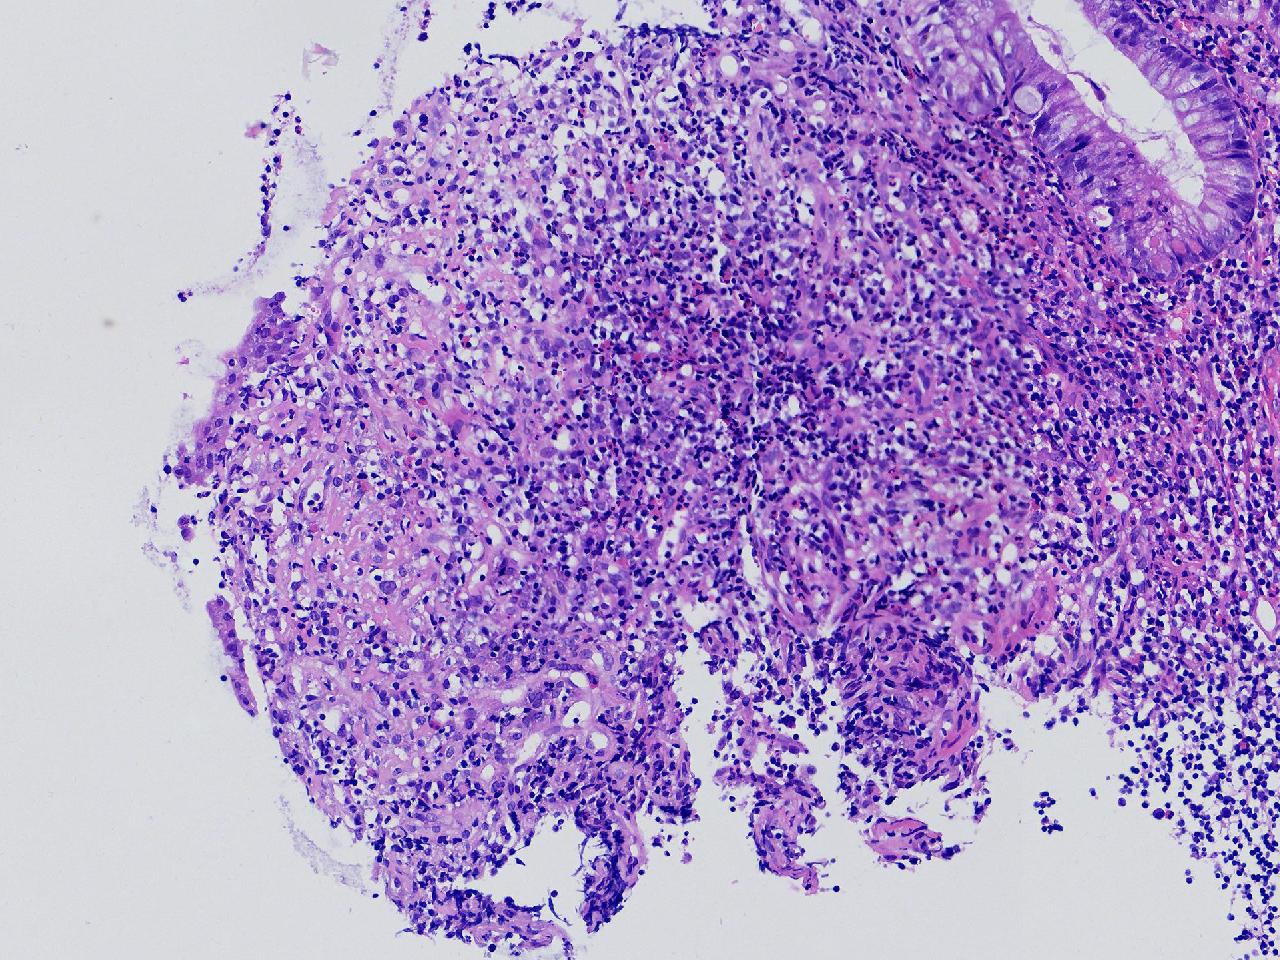

男,62岁,回盲部附近见多发片状溃疡,底覆薄白苔,周围粘膜充血水肿,活检2块,质软,弹性可。

回盲部活检

灰白色不整形软组织2块,直径均0.2厘米。

考虑:溃疡性结肠炎?

炎症性肠病要考虑,具体的类型不太好确定,需要结合临床。

上级医院会诊,不除外炎症性肠病,结合临床。